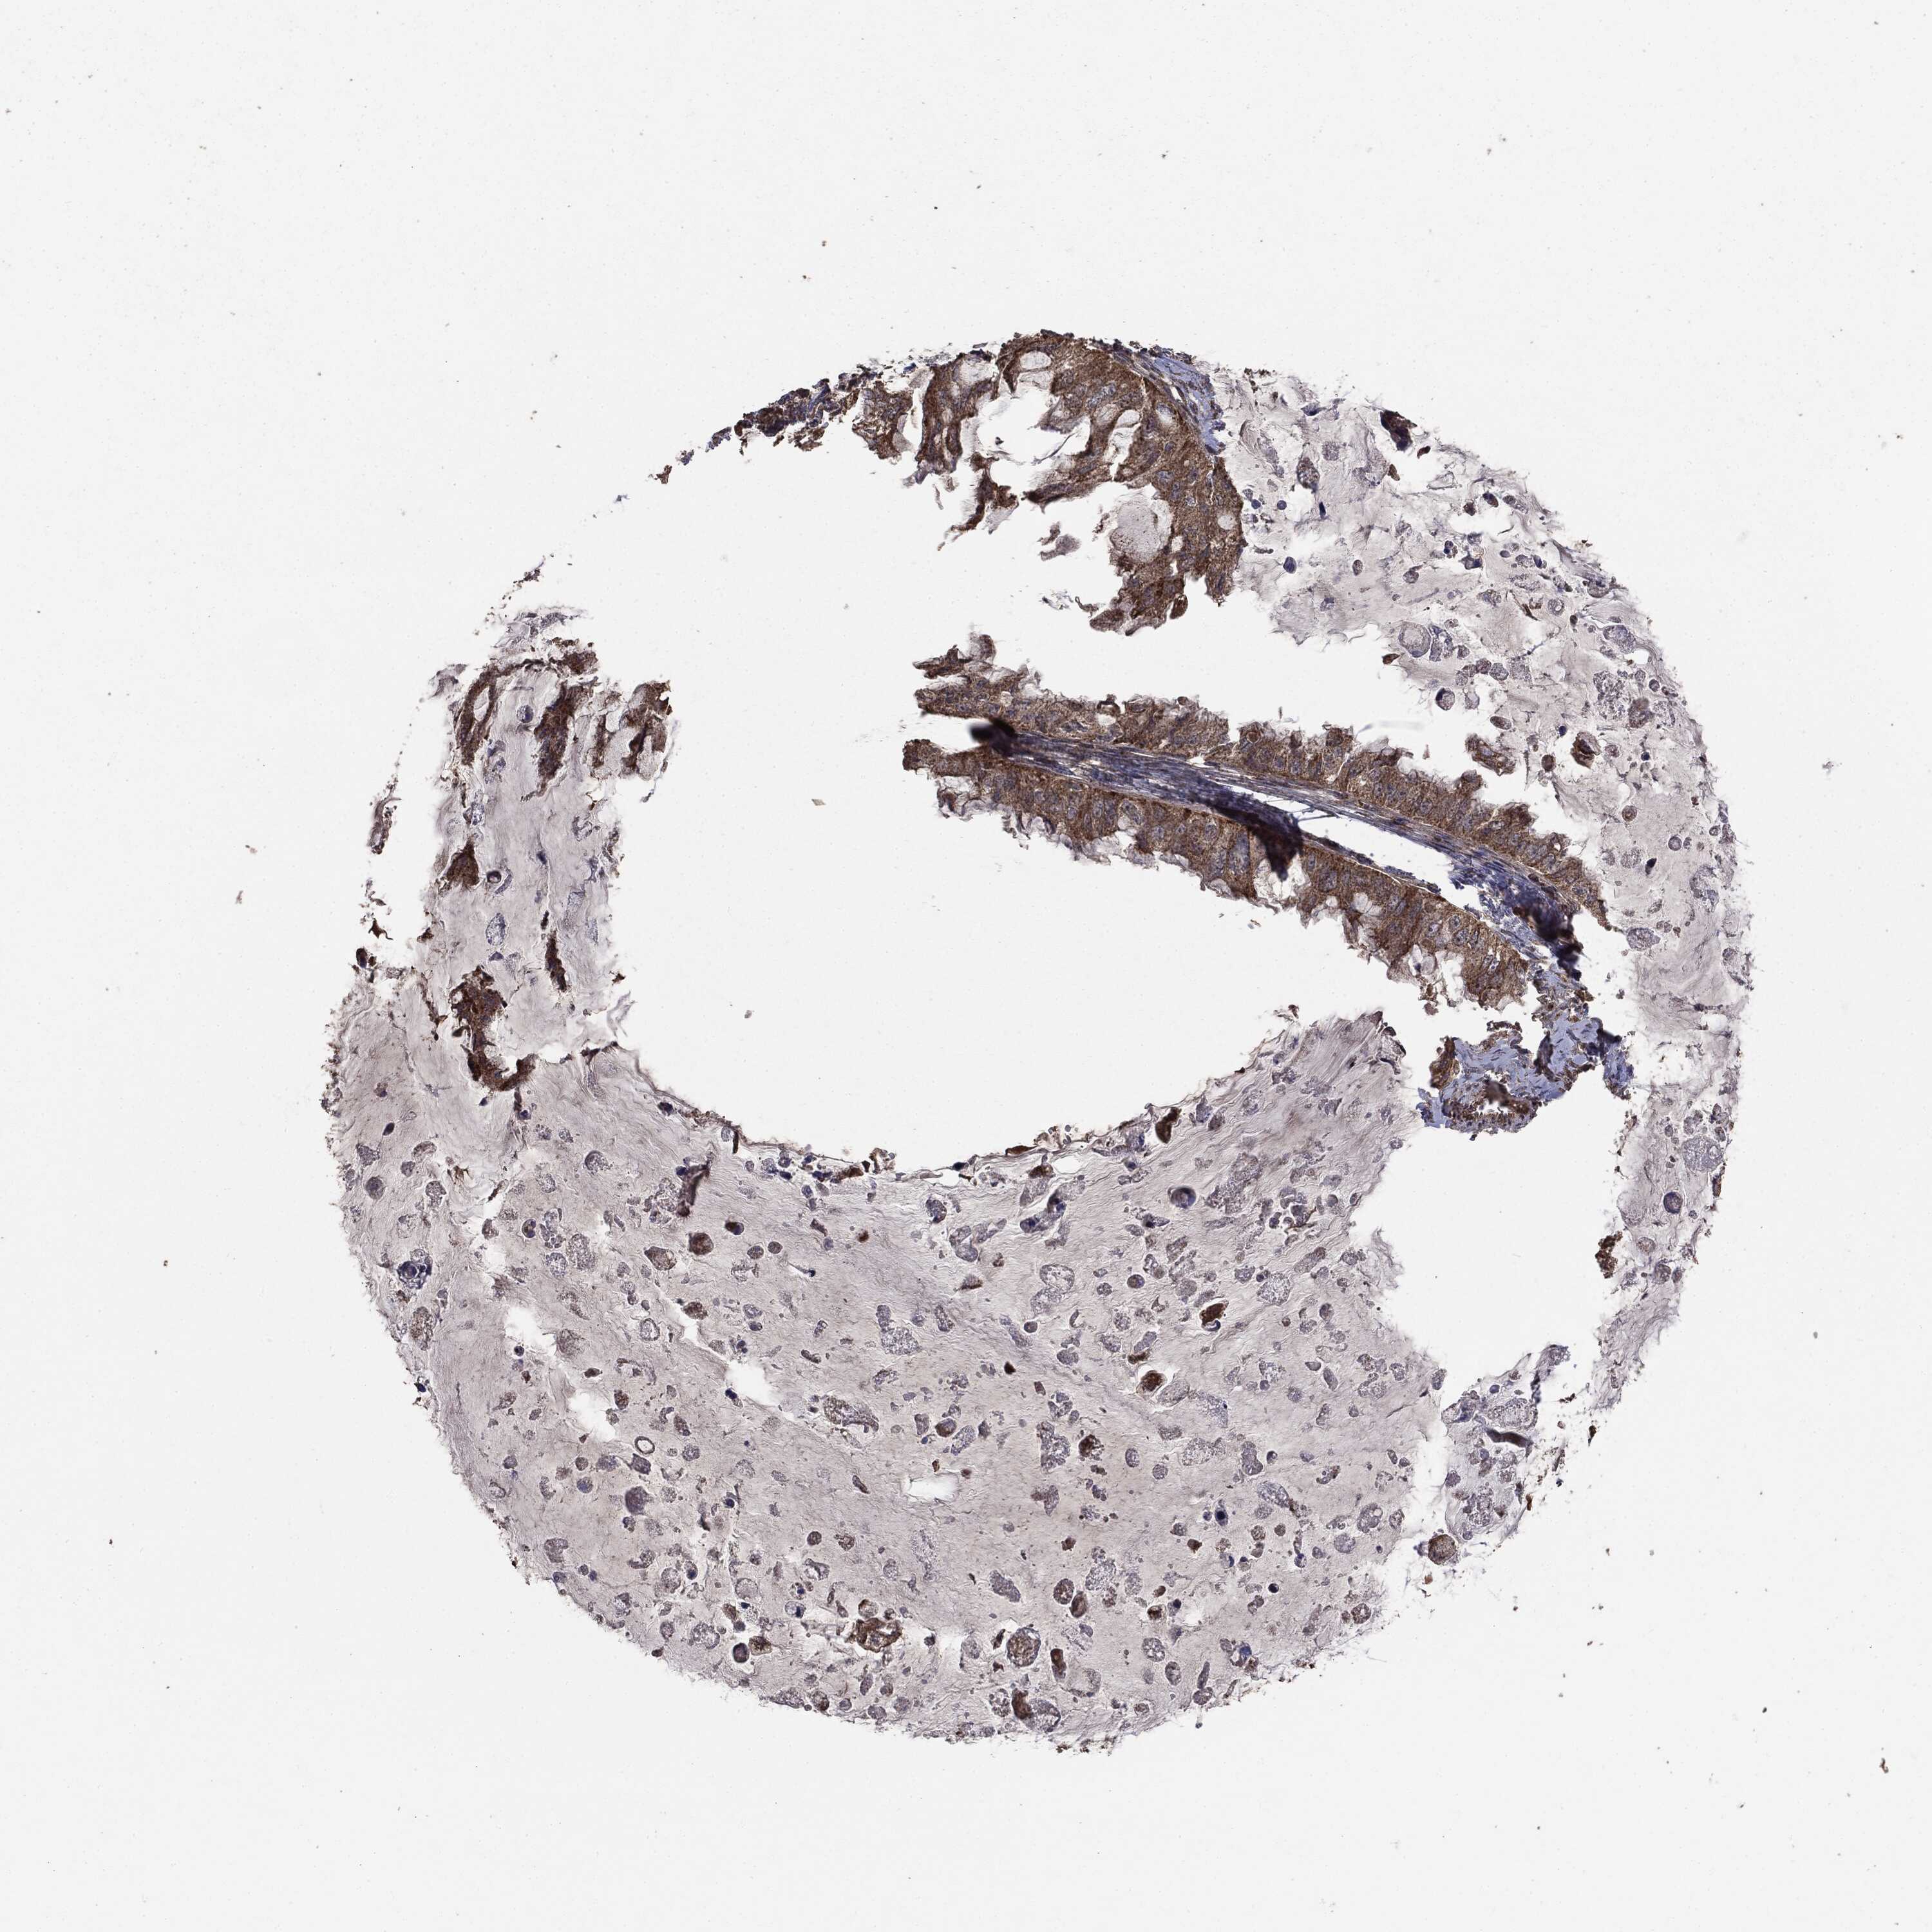

OVARIAN CANCER - Protein expressioni

A mouse-over function shows sample information and annotation data. Click on an image to view it in a full screen mode. Samples can be filtered based on level of antibody staining by selecting one or several of the following categories: high, medium, low and not detected. The assay and annotation is described here.

Note that samples used for immunohistochemistry by the Human Protein Atlas do not correspond to samples in the TCGA dataset.

Antibody stainingi

Antibody staining in the annotated cell types in the current human tissue is reported as not detected, low, medium, or high, based on conventional immunohistochemistry profiling in selected tissues. This score is based on the combination of the staining intensity and fraction of stained cells.

Each image is clickable and will lead to virtual microscopy that enables deeper exploration of all samples and also displays staining intensity scores, fraction scores and subcellular localization as well as patient and tissue information for each sample.

Carcinoma, endometroid